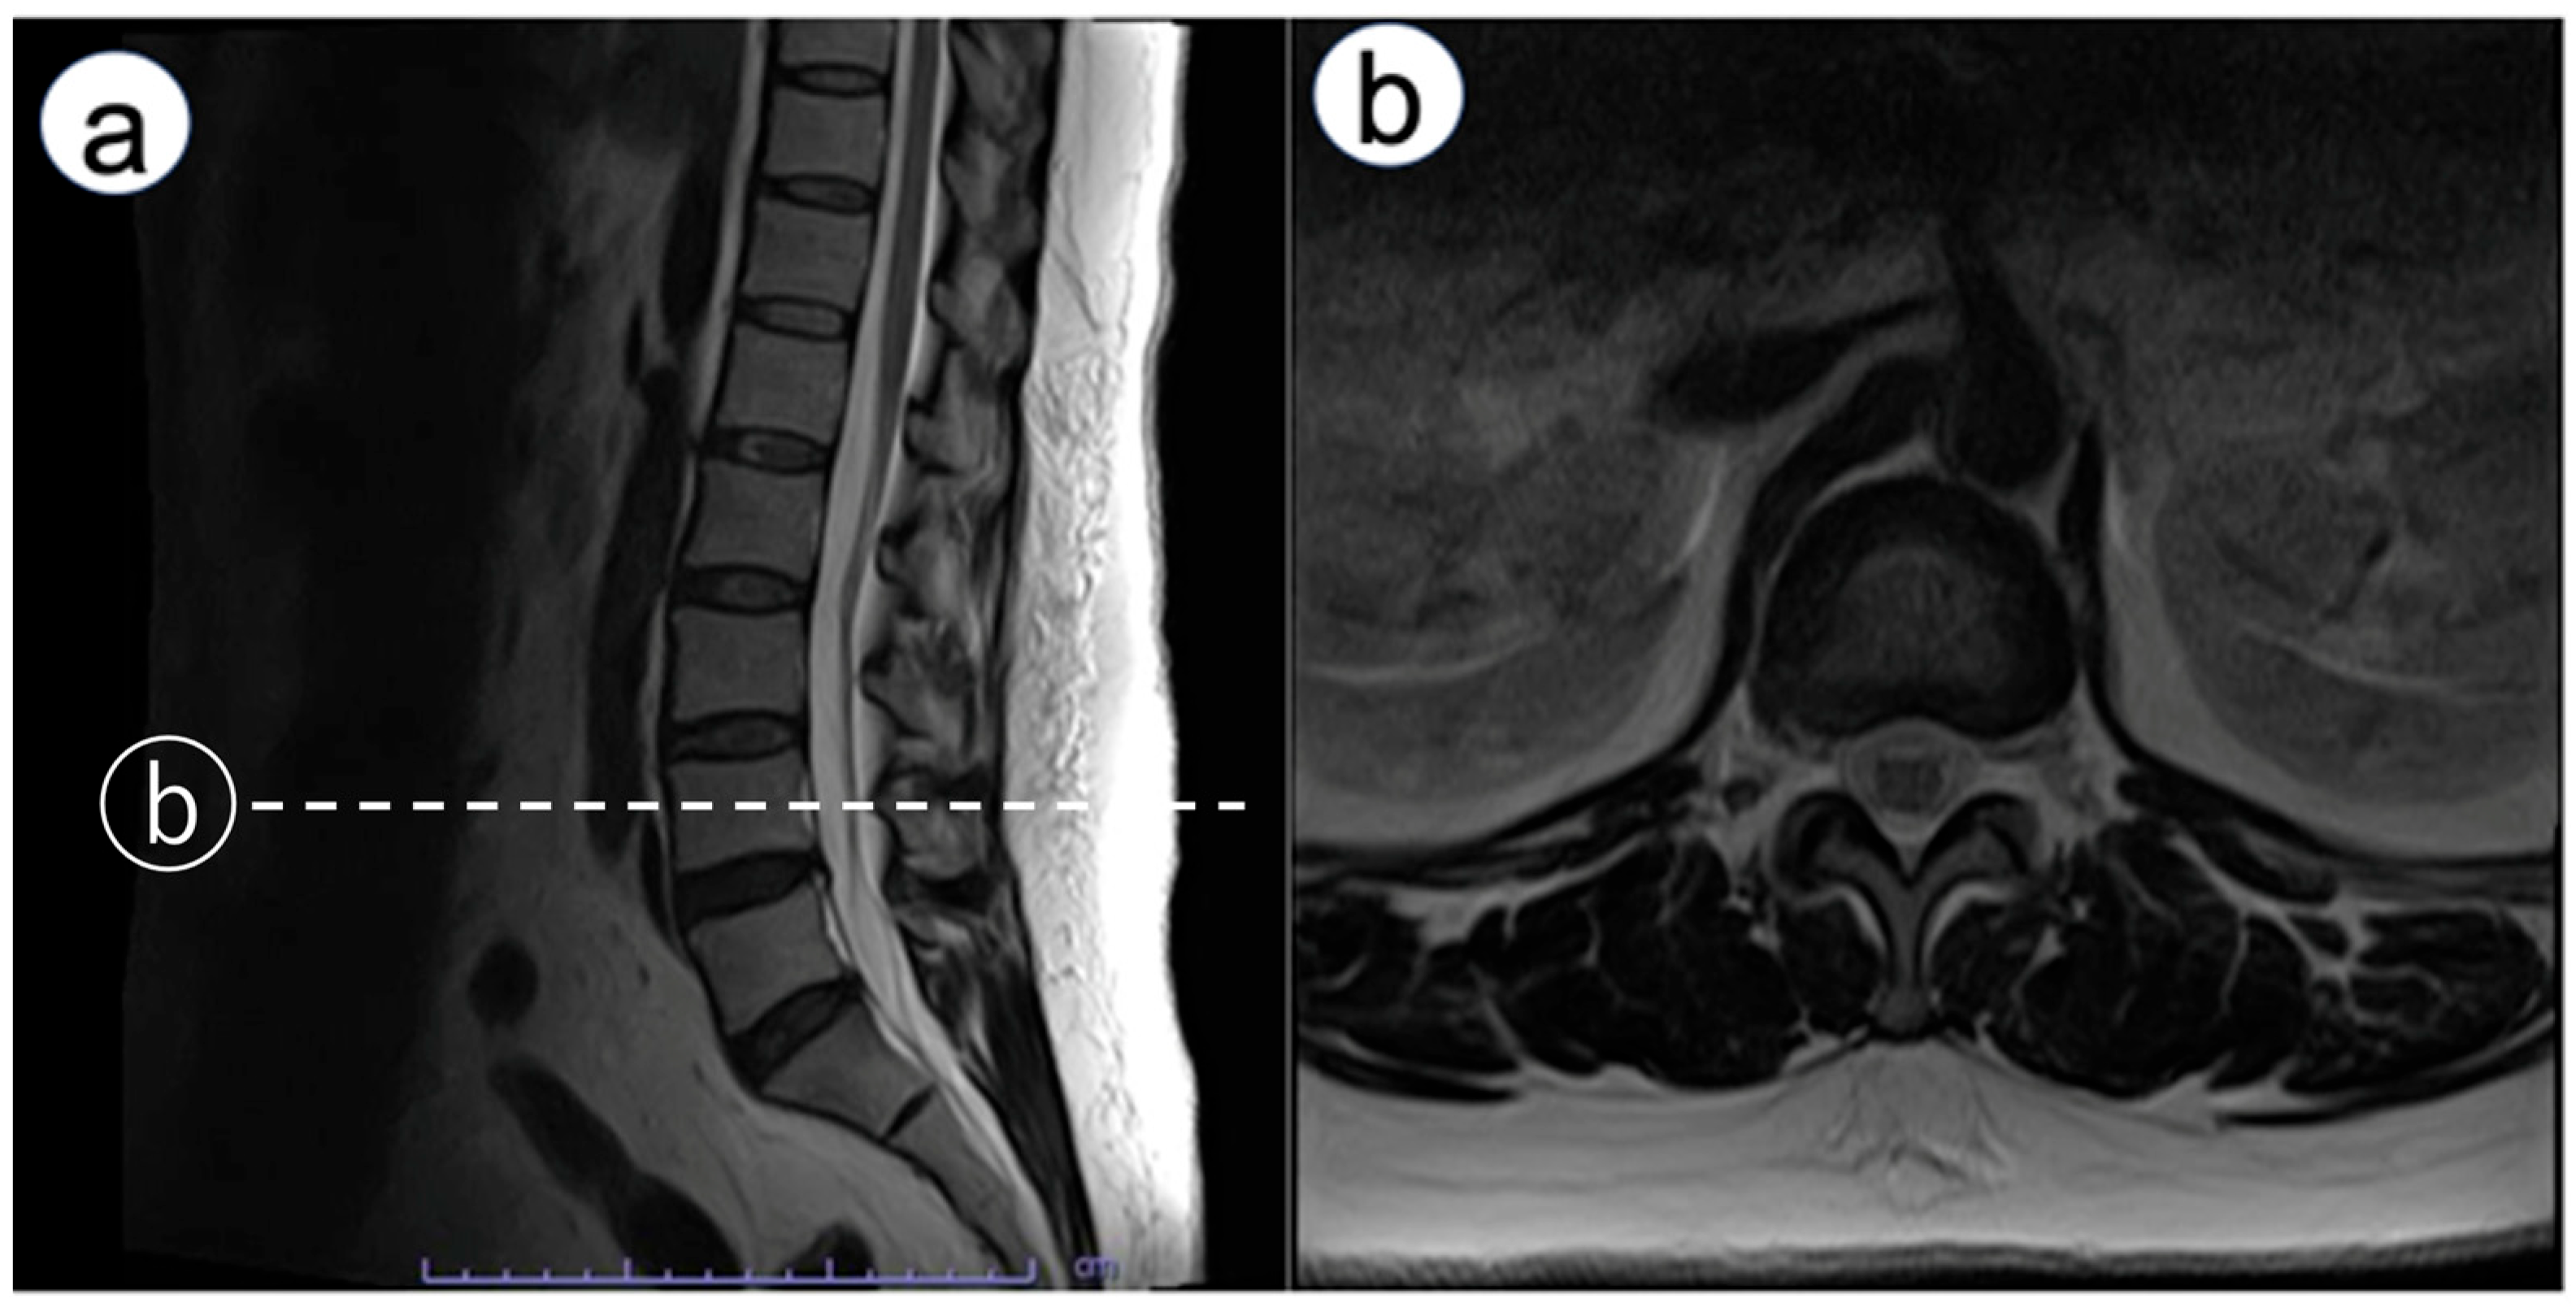

Immediately after emerging from anesthesia, numbness was observed in the left third to fifth fingers. An ultrasound exam was conducted to rule out nerve injury caused by hematoma from arterial catheterization. It found no hematoma around the nerve, and no signs of nerve injury such as swelling were observed in the median nerve or the superficial branch of the radial nerve. Neurological examination revealed bilateral upper-limb weakness. Manual muscle testing (MMT) showed deltoid and biceps brachii strength of 2/5 on both sides, with triceps strength preserved at 4/5. Distal weakness was more pronounced on the left (wrist extensors 3/5, wrist flexors 3/5), compared with the right (4/5 for both). Sensory disturbance was present below the acromion bilaterally. The attending physician consulted an orthopedic surgeon. The exam showed negative Tinel’s and Phalen’s tests, indicating no entrapment neuropathy at the carpal tunnel, but spondylosis was suspected. A magnetic resonance imaging (MRI) scan was scheduled for the following day. However, symptoms improved by postoperative day (POD) 1. On POD 1, bilateral lower limb weakness occurred. Reducing the continuous epidural infusion (0.125% levobupivacaine) from 4 to 2 mL/h alleviated muscle weakness. Yet, electric shock-like pains and numbness appeared in the right lateral thigh. Lumbar MRI showed no epidural hematoma but revealed mild L4/5 disk herniation and bilateral foraminal stenosis (Figure 1). Discontinuing the epidural infusion improved motor function, but MMT indicated iliopsoas muscle weakness. Detailed muscle testing showed right iliopsoas strength of 1/5, right hamstring strength of 5/5, right quadriceps strength of 4/5, right tibialis anterior strength of 4/5, and right gastrocnemius strength of 5/5. The right patellar tendon reflex was slightly diminished, while the Achilles tendon reflex was preserved. In addition, sensory examination revealed decreased sensation in the right lateral thigh, rated 0–1/10. Pregabalin was started for neuropathic pain. After beginning pregabalin, the shock-like pain disappeared; however, dull sensation, numbness, and muscle weakness in the right thigh persisted. The patient was discharged on POD 10 using axillary crutches. At POD 150, sensory disturbances and gait issues persisted, though she could perform daily activities with medication adjustments and outpatient rehabilitation. Two years later, she transitioned from axillary crutches to Lofstrand (forearm) crutches. Subsequently, she was diagnosed with diabetes mellitus with an HbA1c of 8.2%.

Figure 1. Lumbar magnetic resonance imaging. Sagittal and axial MRI images showing no evidence of epidural hematoma, with mild L4/5 disk herniation and bilateral foraminal stenosis. (a): sagittal view, (b): axial view (L4 level, dotted line).